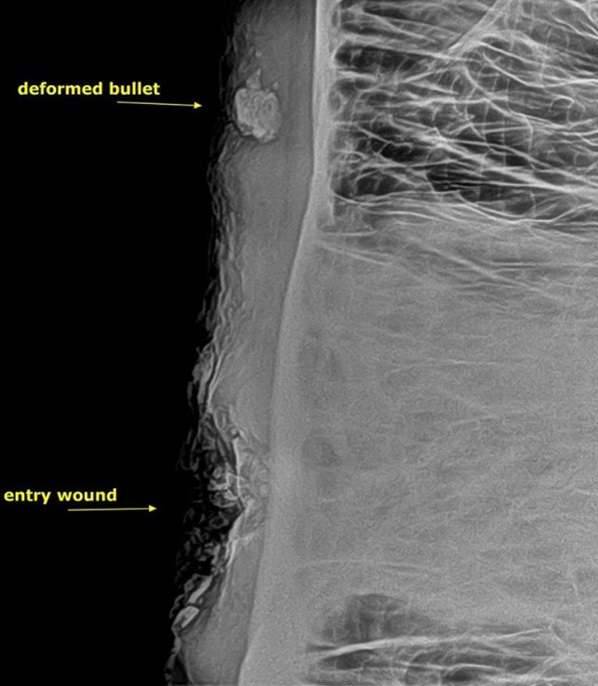

▼他们决定替大象做X光检测,很快发现子弹碎片留在头骨的上方,距离伤口有一段距离。只要再深入几许,这头大象可能就会因此而毙命。